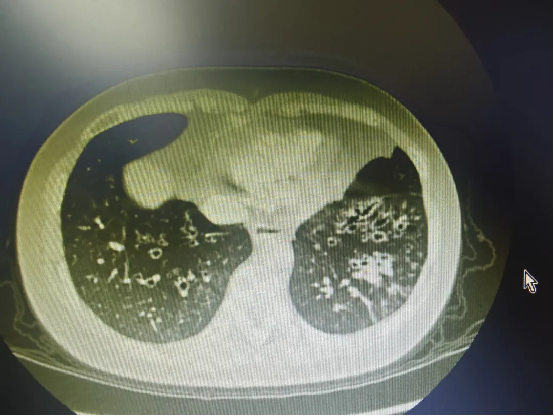

· 影像学金标准——胸部高分辨率CT:这是诊断和评估支扩范围、类型的首要方法。CT上可清晰看到支气管呈囊状、柱状或串珠状扩张,支气管壁增厚,有时可见轨道征印戒征

患者的胸部CT证实了左下肺存在典型的囊柱状支气管扩张。住院后,主管医生根据痰培养结果给予敏感抗生素静脉滴注,同时康复治疗师每日指导他进行体位引流和呼吸训练。因痰液浓稠且量大,初始排痰效果欠佳,经评估后,孙主任为他安排了一次支气管镜下肺泡灌洗治疗。术后,患者当即感觉呼吸顺畅了许多,每日痰量显著减少。